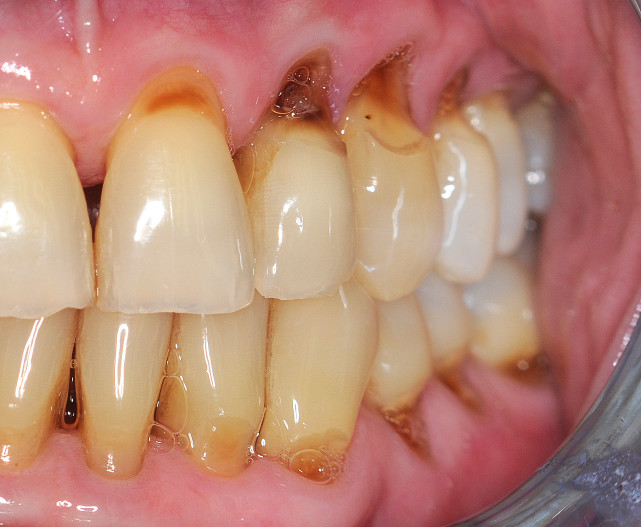

Wurzelkaries

Die Wurzelkaries ist stark assoziiert mit fortschreitendem Alter und gingivalen Rezessionen. Ihr Auftreten wird begünstigt durch eine ungenügende Belagentfernung, diätische Gewohnheiten und einen verminderten Speichelfluss.2 Kariöse Zahnhalsdefekte – besonders im Approximalbereich des Zahnhalses bzw. der Wurzeln – sind sehr schwierig zu restaurieren und bereiten dem Zahnarzt häufig große Probleme (Abb. 2a und b).